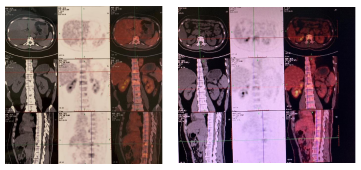

2017.3.31:患者因咳嗽两月入院复查,PET-CT示(如图1):T11椎体,L1椎体糖代增高影,伴混合性骨质破坏影,考虑骨多发转移;右上肺前段、右肺中叶、右肺下叶后基底段近胸膜处、左上肺前段、左下肺背段结节影,部分伴糖代谢轻度增高,多考虑多发转移瘤。

图1 PET-CT提示骨多发转移,肺部多发结节考虑转移瘤

肺部结节小,穿刺风险大,患者亦拒绝行肺部穿刺活检。2017年3月开始予以氟维司群 500mg治疗,同时予以唑来磷酸治疗,并且补充钙剂和维生素D3 。2017年9月复查PET-CT(如图2),疗效评价PR。后续继续予以氟维司群和唑来膦酸的治疗。

图2 T11椎体,L1椎体可见糖代谢增高的混合型骨质破坏影,现未见糖代谢增高,考虑治疗后肿瘤细胞处于抑制状态;原右肺中结节较前缩小,糖代谢未见明显增高,考虑治疗后肿瘤细胞处于抑制状态;原右肺上前段、右肺下叶后基底段近胸膜处,左上肺段、左下肺背段多发结节消失,考虑治疗后好转。